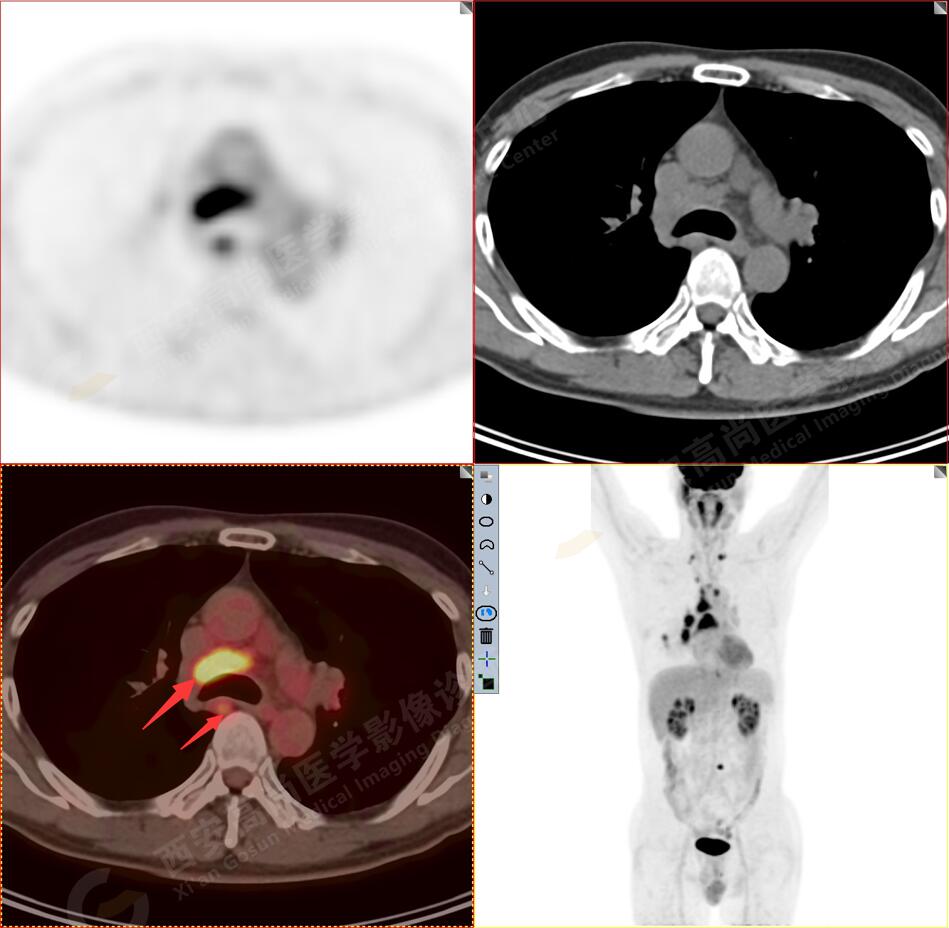

2.以下為全身多發(fā)轉(zhuǎn)移灶

2.雙肺多發(fā)高密度小結(jié)節(jié)灶(最大徑約0.7cm),部分較大結(jié)節(jié)呈FDG代謝略增高,均考慮為轉(zhuǎn)移性病變。

4.右后胸膜輕度增厚,形成多個(gè)條狀軟組織病變,呈FDG代謝輕度異常增高,考慮為轉(zhuǎn)移性病變;右側(cè)胸腔微量積液。

5.腰4椎體左側(cè)緣溶骨性骨質(zhì)破壞,F(xiàn)DG代謝異常增高,考慮骨轉(zhuǎn)移瘤。